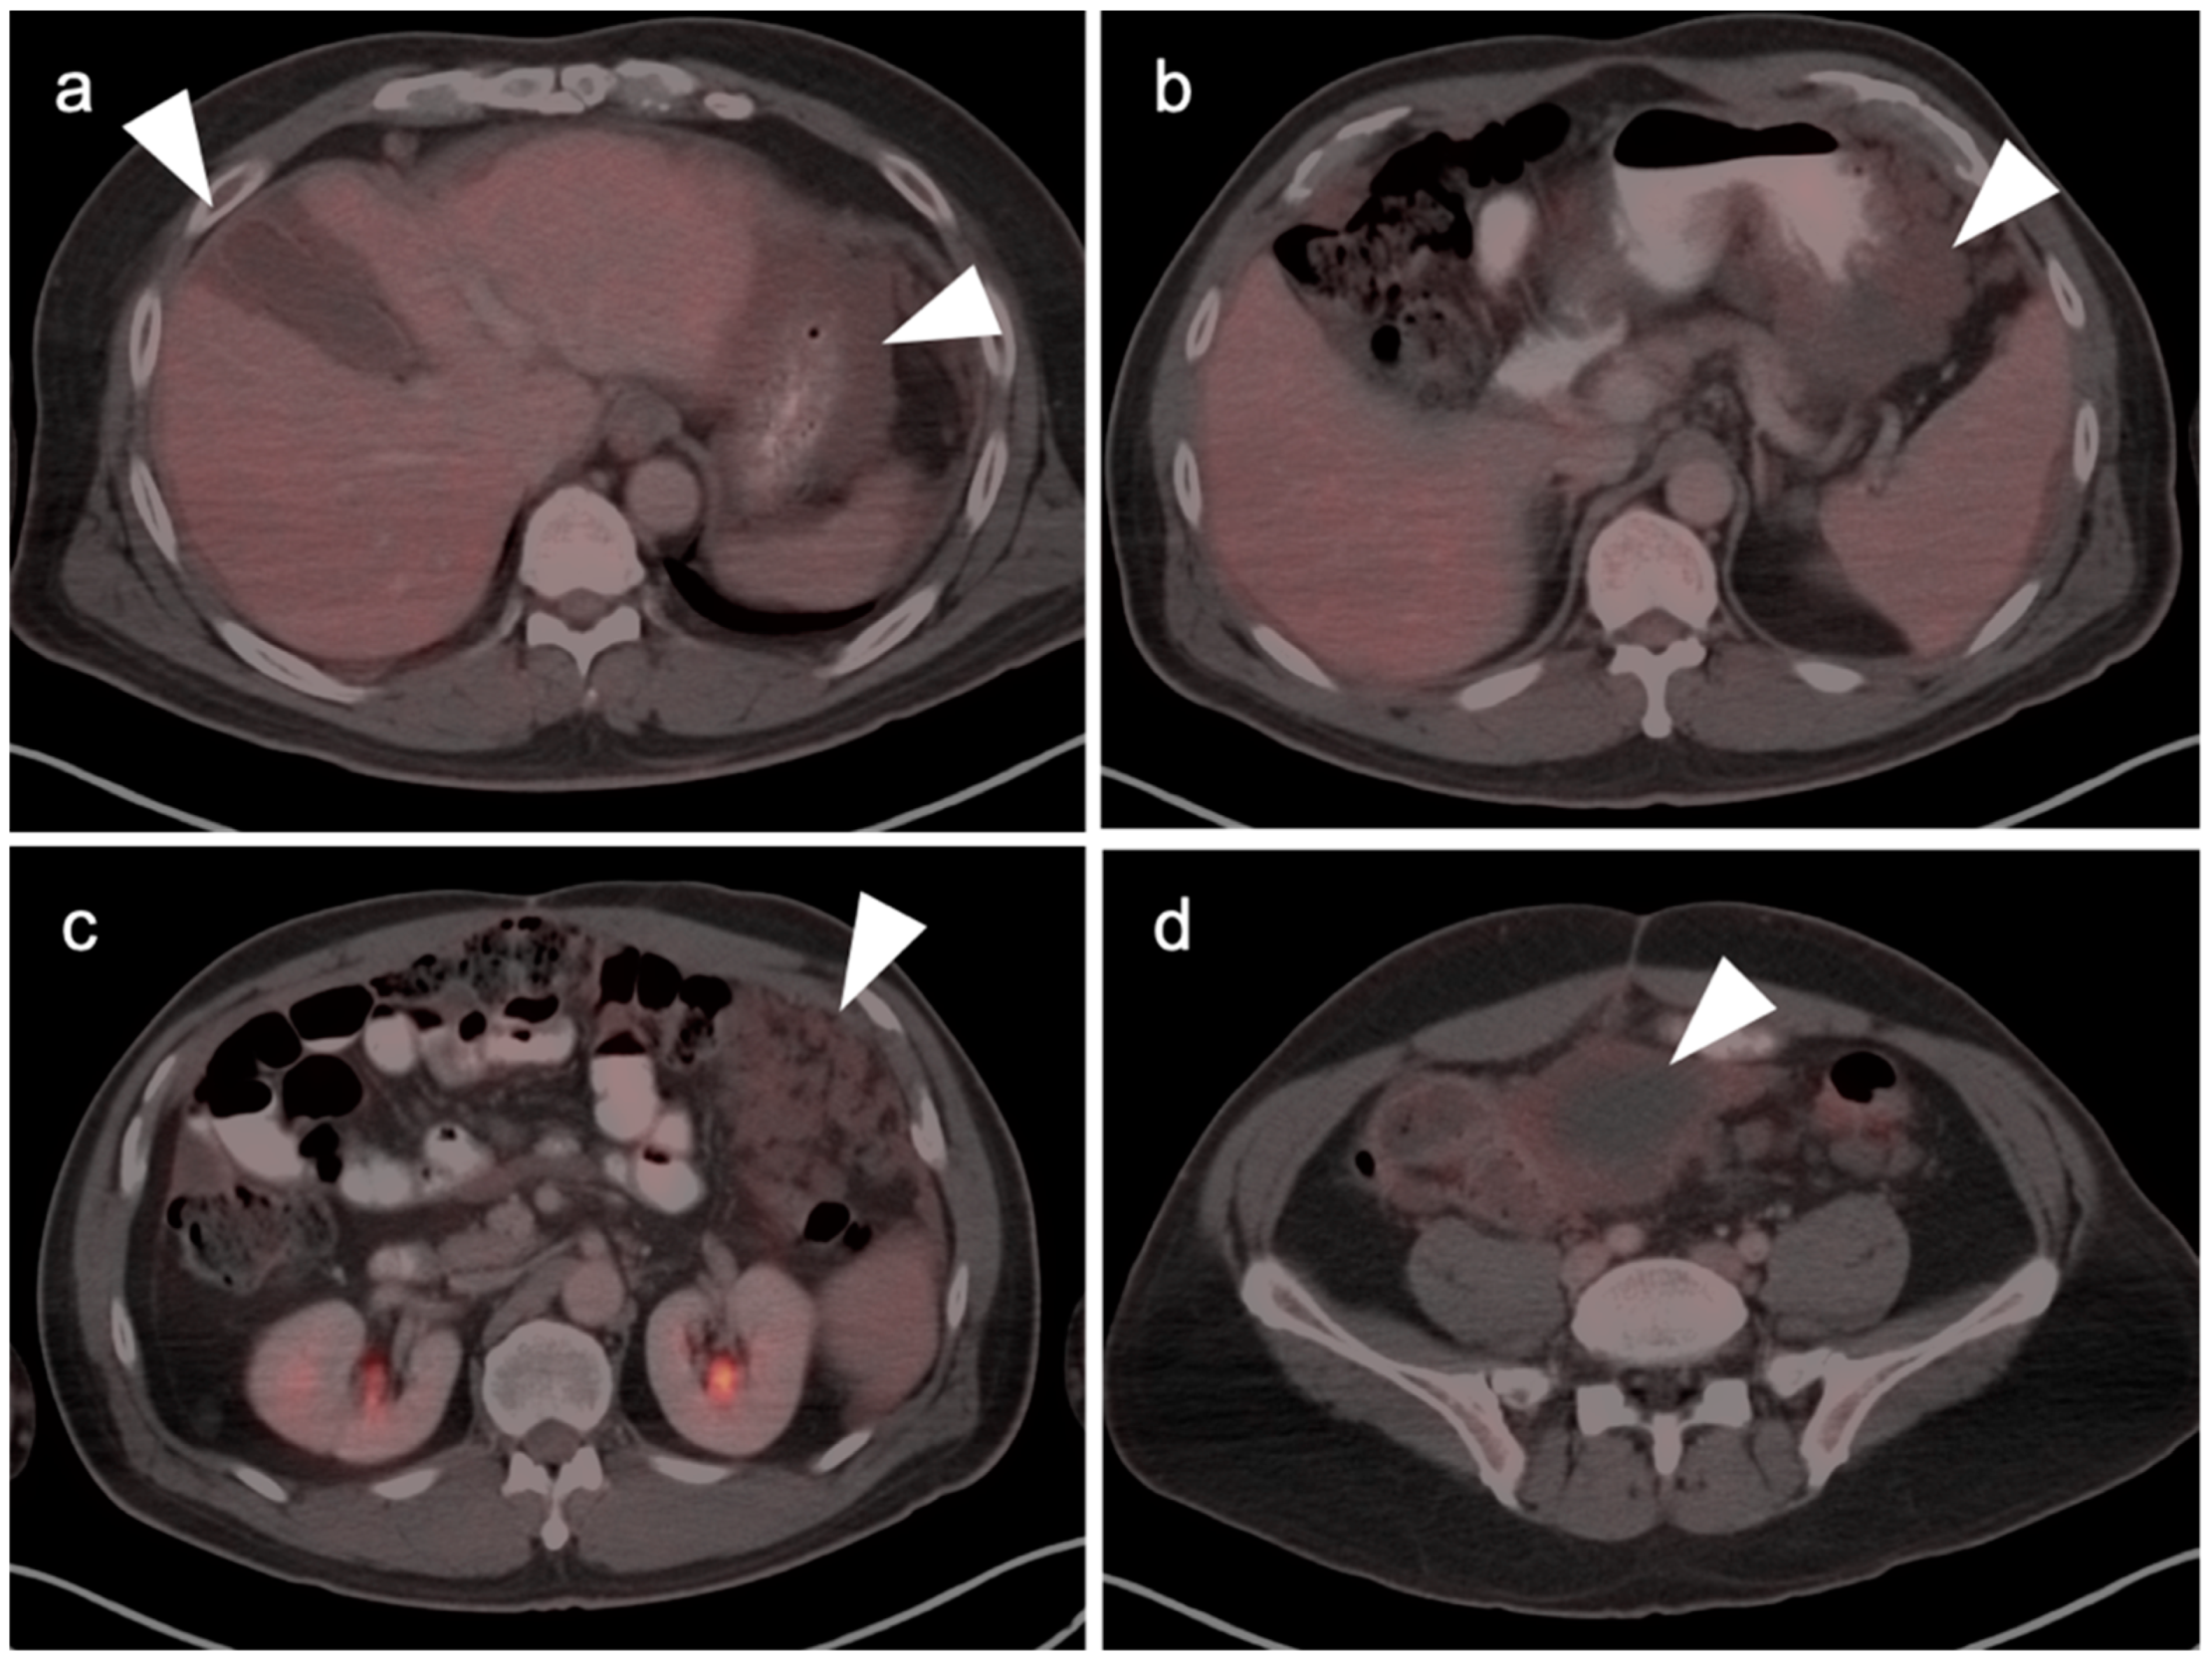

10. Anal Carcinoma